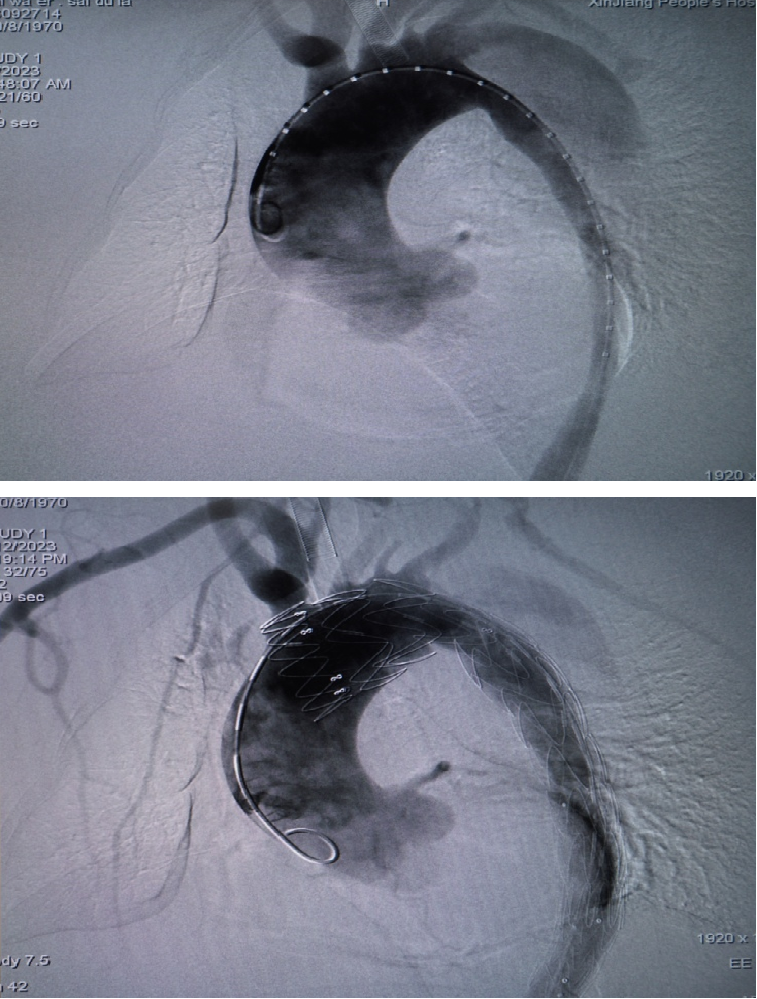

★ 典型病例

▎病例一

男性,44岁,慢性B型夹层。2010年12月行TEVAR术。

2013年5月发现RTAD,未处理。2015年2月死亡。

▎病例二

男,52岁,慢性夹层。2015年8月入院,4年前曾因B型层行TEVAR术,主动脉解剖变异,扭曲。行双烟囱+TEVAR术。术后第3天RTAD ,死亡。

▎病例三

男,60岁,慢性夹层。2013年12月行Debranching+TEVAR术 。2016年7月复查: RTAD ,未手术。失访。

▎病例四

男, 49岁,急性夹层 。2018年11月TEVAR。一月后复查:RTAD 。 2019年1月双开窗。2019年4月2日 复查,结果良好。

▎病例五

男,49岁,急性AD。2019年1月TEVAR,3月RTAD,行全弓置换+支架象鼻。2022 年1月25日术后复查,结果良好。

▎病例六

男,50岁,急性夹层。2019年5月TEVAR,术后第4天出院, 意识丧失,死亡。 RTAD ?

▎病例七

男,54岁,急性夹层。 2023年6月入院,行Debranch+TEVAR。术后出院第四天死亡。 RTAD ?

RTAD治疗的“金标准”仍是开放修复。7例RTAD患者转心外科行全弓置换+支架象鼻,7例痊愈。腔内修复在Z0区再次TEVAR很可能再次RTAD。